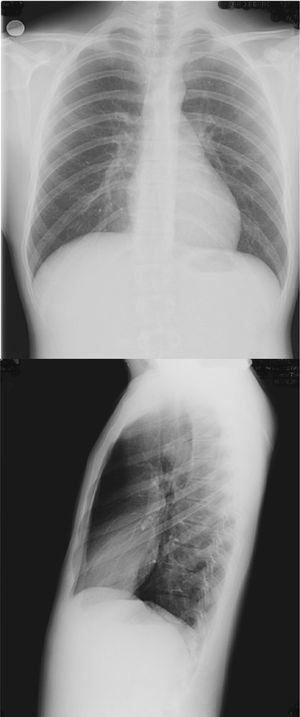

En Neumología se realizó una prueba diagnóstica (fig. 3).

Figura 3. Tomografía axial computarizada de tórax.

En Neumología se realizó una tomografía axial computarizada (TAC) de tórax, en la que aparecía una lesión polipoidea sésil con crecimiento endoluminal intratraqueal desde la pared posterolateral derecha a 20 mm de la carina (a la altura del cayado de la ácigos), de tamaño 20 3 14 3 11 milímetros de tamaño, que producía estenosis evidente de la luz traqueal.